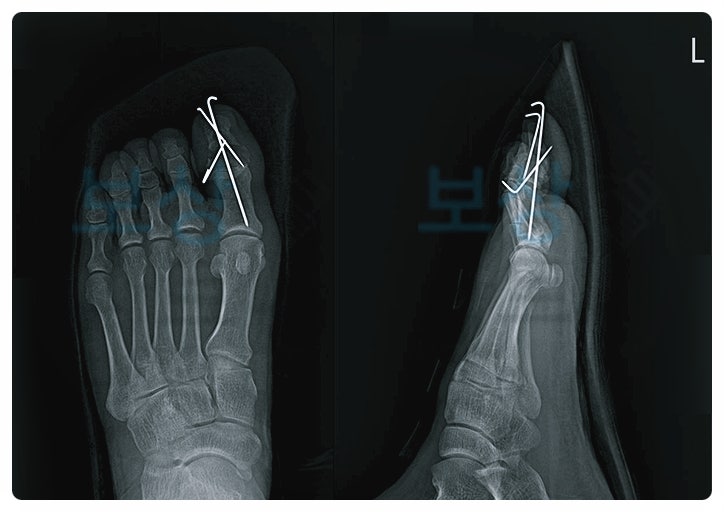

주요 처치는 비관혈적 정복술 후 금속핀 고정술을 통해, 골절 부위를 맞추고 안정화시키는 방식이었습니다. 절개를 크게 하지 않아 비교적 빠른 회복을 기대할 수 있는 수술이나, 이후 석고 부목 고정 상태로 약 한 달 이상 움직임을 최소화해야 했습니다.

그리고 제3 의료기관의 장해 평가 결과, 엄지발가락의 강직 상태로 뚜렷한 기능장애(지급률 8%)로 판정된 진단서를 받을 수 있었는데요. 보험금 심사 과정에서 상대측 보상 담당자는 영구장애가 아니라는 자체 자문 소견을 주장했습니다. 하지만 오랜 경험으로 이러한 분쟁 상황에 적절하게 대응할 수 있었습니다.